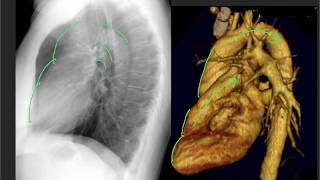

Anatomy on the lateral CXR